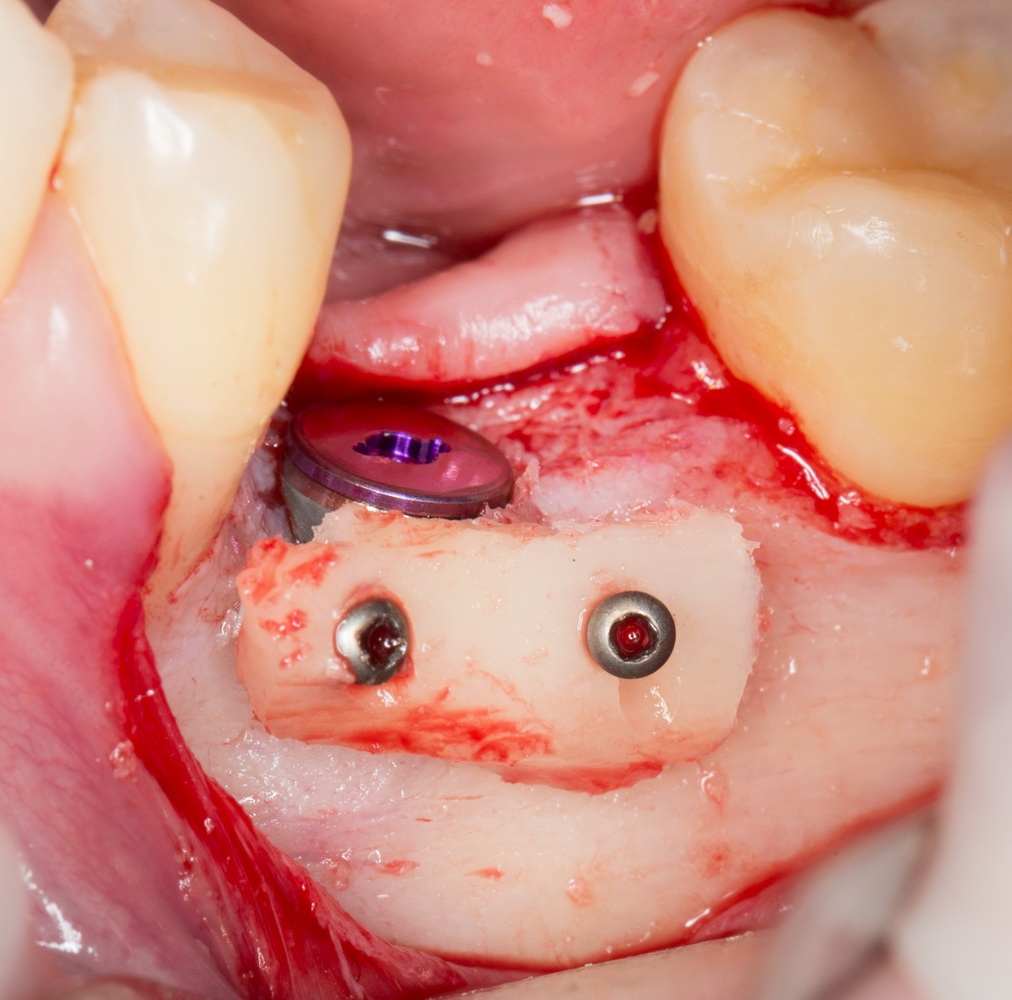

Остеопластика или «наращивание костной ткани» при имплантации — выбор метода и отдаленные результаты.